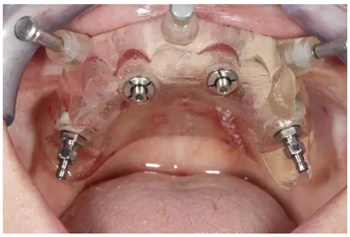

全程引導(dǎo)式手術(shù)

通過固位釘固定上頜NobelGuide外科導(dǎo)板和第一枚已植入的植體和導(dǎo)板基臺(tái)。

4枚NobelReplace CC RP4.3植體(11.5mm 軸向植體和13mm 傾斜植體)已植入完成:前牙區(qū)植體上裝配的是導(dǎo)板基臺(tái),后牙傾斜植體上裝配的是內(nèi)錐形連接的引導(dǎo)式持釘器。